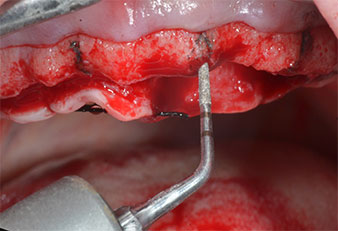

Пиезоелектрически инструмент с диамантено покритие с форма на пламък (Piezomed I1) e използван за маркиране на позициите на имплантите и за пилотна подготовка (Фиг. 3). Препарацията беше извършена с внимателни вертикални движения, с намалена мощност, пълна иригация и лек натиск (под 300 g) След това се приложи пилотен инструмент (Piezomed I2A/ I2P) за първоначално увеличение на диаметъра на имплантното ложе с 2 mm (Фиг. 4), последвано от 3 mm разширение (Фиг. 5)